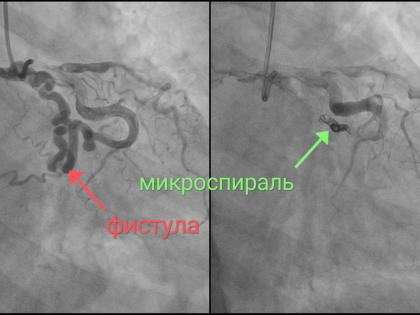

Уникальную операцию провели в Региональном сосудистом центре Новгородской областной клинической больницы

Эмболизация коронаро-легочной фистулы — патологического сообщения между коронарной и легочной артериями (в данном случае — с легочным стволом).